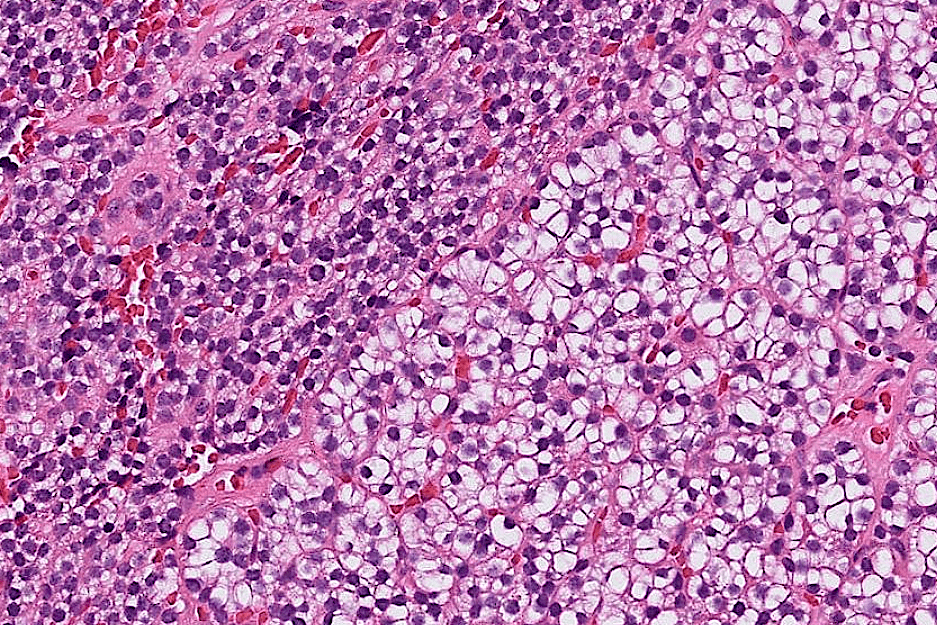

breast cancer

hepatocellular carcinoma